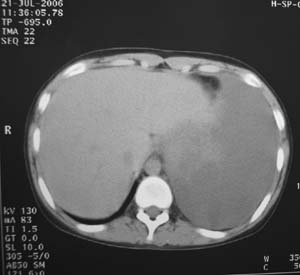

左肺巨大肿块,内散在斑点状高密度骨化影,右肺见多发结节灶,双侧胸膜局限性增厚。有骨肉瘤病史,支持骨肉瘤手术后转移。

病史及影像表现支持骨肉瘤术后肺转移